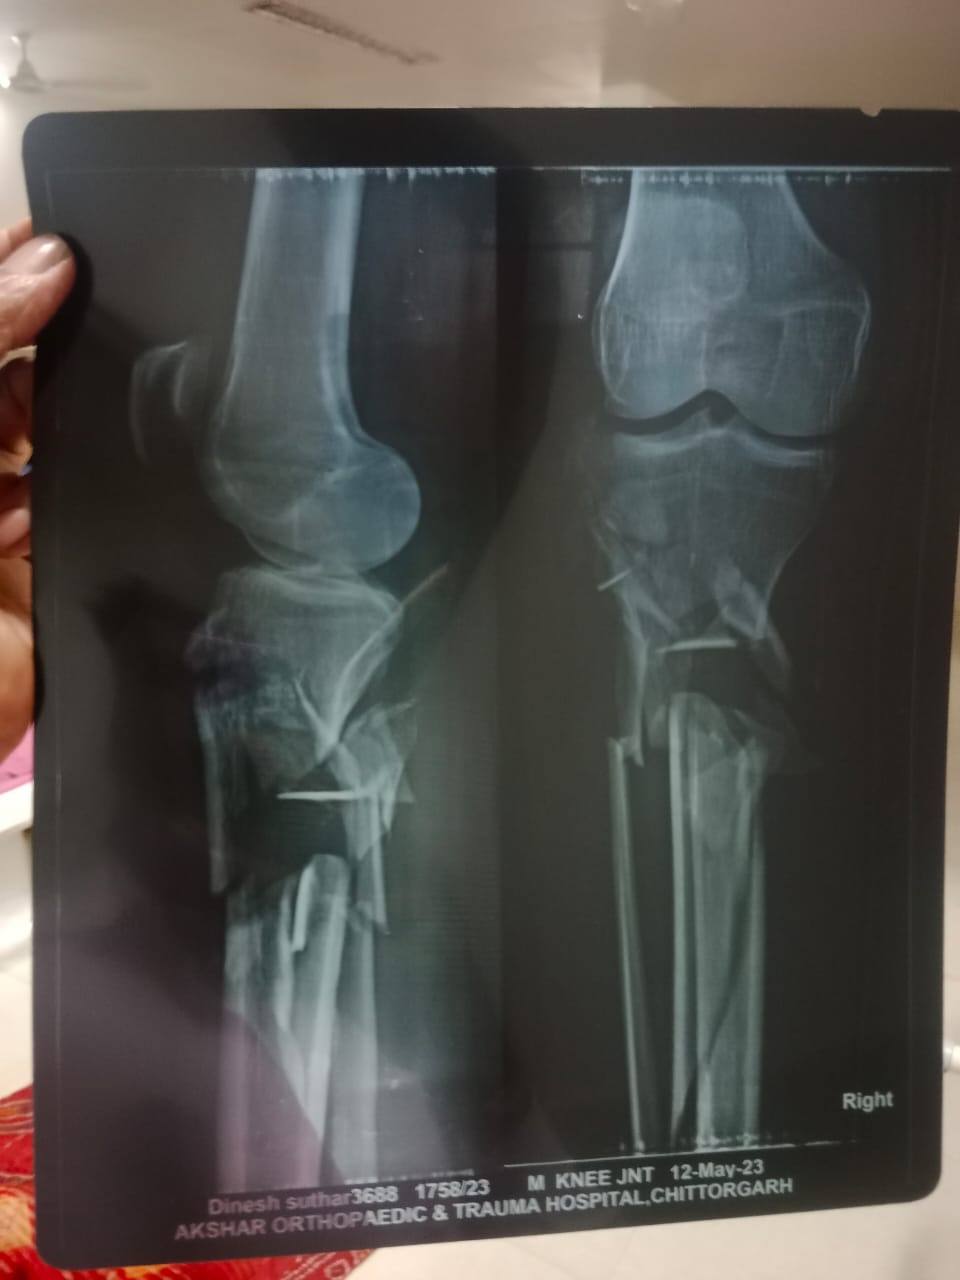

Vikas Suthar